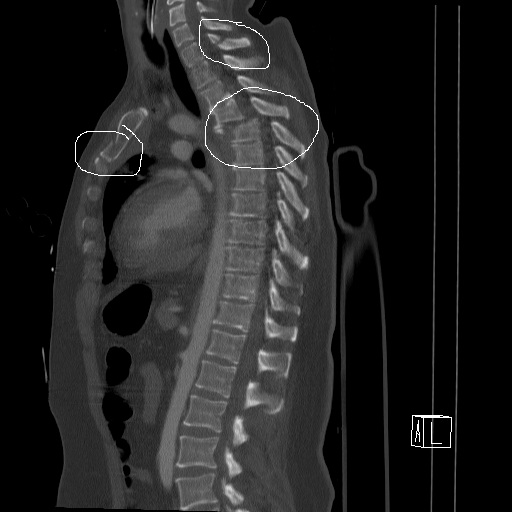

Вложение не в текстовом формате было извлечено&hellip;

Имя     : коронарная1.jpg

Тип     : image/jpeg

Размер  : 58423 байтов

Описание: отсутствует

Url     : http://weborto.net:8080/pipermail/ortho/attachments/20121017/f0f92842/attachment-0002.jpg

Имя     : сагитальная1.jpg

Размер  : 57743 байтов

Url     : http://weborto.net:8080/pipermail/ortho/attachments/20121017/f0f92842/attachment-0003.jpg